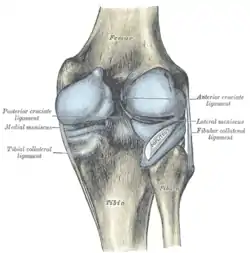

Intracapsular

The knee is stabilized by a pair of cruciate ligaments. These ligaments are both extrasynovial, intracapsular ligaments.[17] The anterior cruciate ligament (ACL) stretches from the lateral condyle of femur to the anterior intercondylar area.[13] The ACL is critically important because it prevents the tibia from being pushed too far anterior relative to the femur.[13] It is often torn during twisting or bending of the knee.[18] The posterior cruciate ligament (PCL) stretches from medial condyle of femur to the posterior intercondylar area. This ligament prevents posterior displacement of the tibia relative to the femur.[13] Injury to this ligament is uncommon but can occur as a direct result of forced trauma to the ligament.

The transverse ligament stretches from the lateral meniscus to the medial meniscus. It passes in front of the menisci. It is divided into several strips in 10% of cases.[10]:208 The two menisci are attached to each other anteriorly by the ligament.[19] The posterior (of Wrisberg) and anterior meniscofemoral ligaments (of Humphrey) stretch from the posterior horn of the lateral meniscus to the medial femoral condyle. They pass anterior and posterior to the posterior cruciate ligament respectively.[13][10]:208 The meniscotibial ligaments (or "coronary") stretches from inferior edges of the menisci to the periphery of the tibial plateaus.